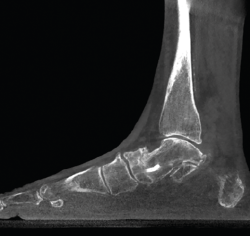

Figura 4. Estudio de la articulación subtalar bilateral.

- Patología y deformidad subtalares. Estudio de la configuración subtalar y artropatía de la misma (Figura 4).

La medición de las caras articulares anterior, media y posterior de la articulación subtalar se complica en un estudio simple radiográfico. La inclinación-orientación de las mismas en relación con la configuración del retropié y su implicación en el medio y antepié han sido estudiadas con la TAC en carga(8).